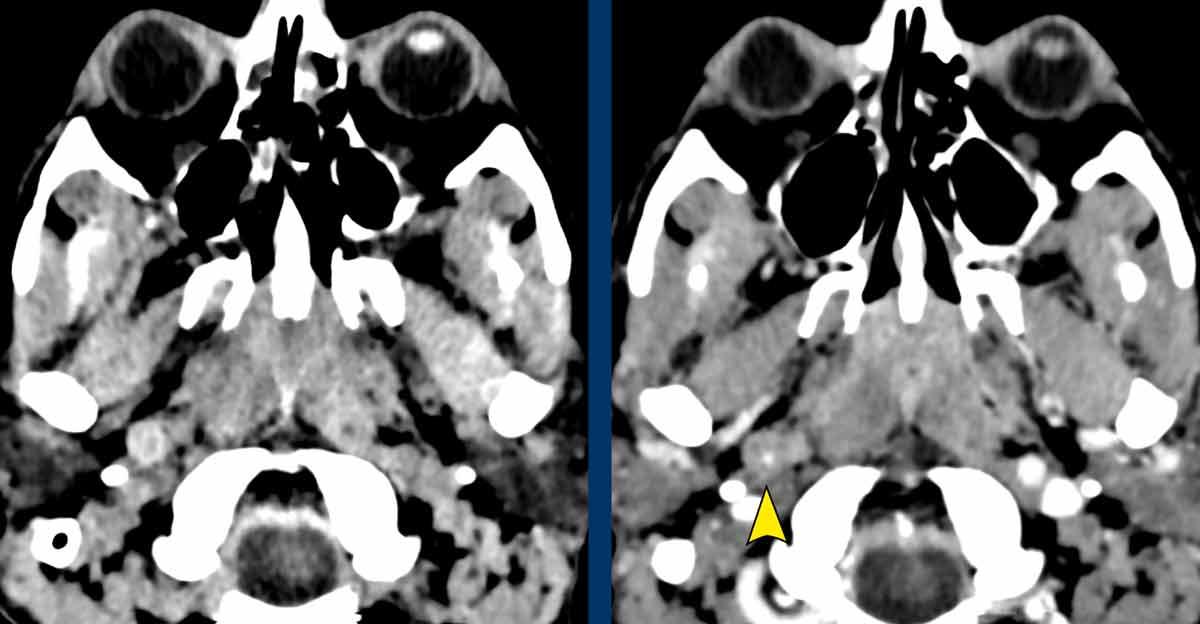

CT lúc nhập viện cho thấy gãy mỏm ngang C7 và gãy xương sườn thứ nhất (đầu mũi tên).

Trên CECT có hiện tượng thoát thuốc cản quang cho thấy đang chảy máu tích cực (vòng tròn).

Continue with the MRI…

Đầu tiên, siêu âm vùng cổ được thực hiện để tìm kiếm tổn thương đứt rễ thần kinh, tuy nhiên việc khảo sát này bị hạn chế do các thay đổi chấn thương ở vùng này.

Sau đó, chụp MRI được thực hiện.

Hình ảnh

Hình ảnh cắt ngang cho thấy sự tăng cường tín hiệu của các rễ thần kinh, gợi ý tổn thương đám rối thần kinh cánh tay.

Cũng lưu ý tổn thương phần mềm cạnh cột sống bên phải.

Continue….

Ngoài ra, hình ảnh T2W cho thấy một số tín hiệu cao nhẹ trong tủy sống bên phải (mũi tên).

Điều này được xem là bệnh lý tủy sống sau chấn thương và cũng có thể là giải thích cho hội chứng Horner bên phải.